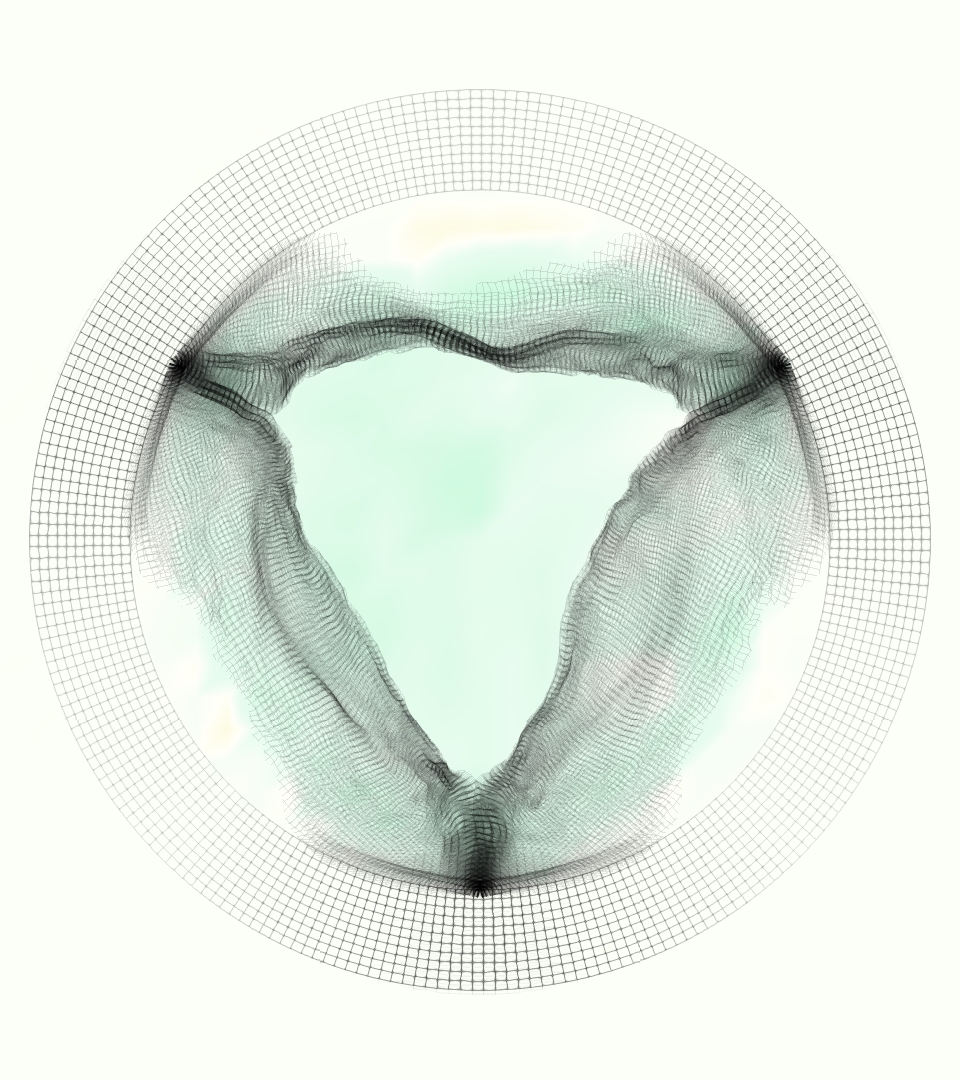

The gross morphology of the model valve that emerged from this process is shown in Figure 4. The free edge was 2.87 cm, corresponding to 3.3 cm in the predicted loaded configuration. After the pinching the leaflets together at the commissures, this left approximately 2.1 cm of free edge rest length per leaflet free to move independently of the other leaflets, within measurement error of ±0.1 cm from the free edge length of 2.2 cm measured on the prostheses. The leaflet rest height was 0.94 cm corresponding to a predicted loaded height of 1.44 cm. The measured leaflet height of 1.3 cm is nearly the predicted loaded height of 1.44 cm, which may be because the leaflets are so compliant in the radial direction, that pulling them flat to measure them achieved substantial stretches. The fiber orientation of the model runs from commissure to commissure and qualitatively matches experimental observations [38], though direct quantitative comparison is beyond the scope of this work. One minor limitation is that we do not add bending rigidity to the leaflets, beyond what emerges from the thickening process described above, and thus may not accurately capture leaflet flutter or other similar behaviors. Based on the thickness of mm, we estimated the mean tangent modulus at the predicted loaded stretches as dynes/cm2 circumferentially and dynes/cm2 radially. The prosthetic valve tissue is fixed in glutaraldehyde, and literature values for the fully-recruited circumferential tangent modulus of fixed porcine aortic valve tissue vary widely. Based on the experimental measurements of Billiar and Sacks and their constitutive law for valves fixed under 4 mmHg of pressure, we evaluated their constitutive law at the relevant stretches and and estimated the circumferential tangent modulus to be dynes/cm2 [6]. Rousseau et al. reported moduli ranging from to dynes/cm2, depending on the applied preload during fixation [36]. Sung et al. reported moduli ranging from to dynes/cm2, depending on fixation pressure [43]. Thus our estimated tangent modulus falls within the range of existing studies, so we considered our resultant modulus in good agreement given the complexity of the steps involved, phenomenological nature of the constitutive law and uncertainties in experiments. We do not have access to the precise material properties of the prosthetic valve, and further, the only literature we could find on the material properties of a similar prostheses reported the tangent modulus at one particular loading, which did not appear to be at a relevant stretch for comparisons with our model [19]. Thus, our model has material properties in a reasonable range for a fixed aortic valve prostheses (placed in the pulmonary position in our simulations), but it does not directly model the material properties of the prostheses.

We constructed the model vessel for FSI simulations from data from the MRI scans (Figure 4). The signal magnitude of 3D printed model material is distinct from the signal of the fluid in the scans, and we applied a thresholding operation to generate a three-dimensional model of the printed vessel surface. Using the MRI data ensured that the MRI and simulation coordinates were consistent in space and there were no alignment or registration errors. While using the files that generated the 3D printed model would have offered more spatial fidelity, the potential error in flow fields due to any mis-registration would have likely been much more substantial. Using Meshmixer (San Rafael, CA), we smoothed the mesh to remove stair-step effects and removed artifacts from the valve scaffold. We then remeshed to the desired edge length of 0.25 mm and extruded the model 0.25 mm and 0.5 mm to create a three-layer structure. As in the valve, this serves to eliminate the “grid aligned artifact” that can occur with pressure differences across thin membranes in the IB method [16]. Flow extenders of length 1 cm were added to the vessel at the inlet and both outlets to ensure that the normal to the vessel was aligned with the normal of the fluid box at the inlets and outlets. In FSI simulations, the vessel was held in place using target points, stiff springs of zero rest length that connect the current position of each model node to its desired position (Section 3.3). Additional linear springs are placed on each edge in the triangulated model. These springs are not meant to model a particular material and only serve to keep the vessel rigid and stationary throughout the simulation.